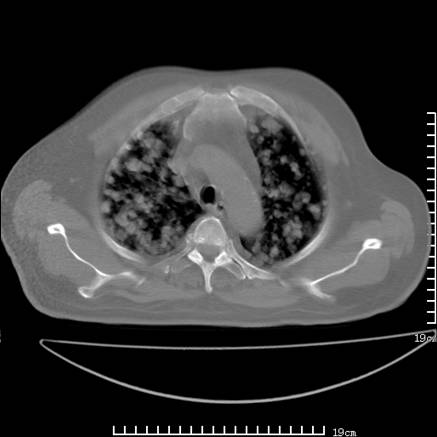

张男,75岁,干咳半年余,小便不利二年,b超检查前列腺增大,未见明显肿块;前列腺癌血生化检查多项指标明显增高。

双肺内多发转移瘤,纵膈淋巴结转移。来源前列腺?建议盆腔mri进一步检查。

双肺转移满了。

两肺广泛转移瘤。